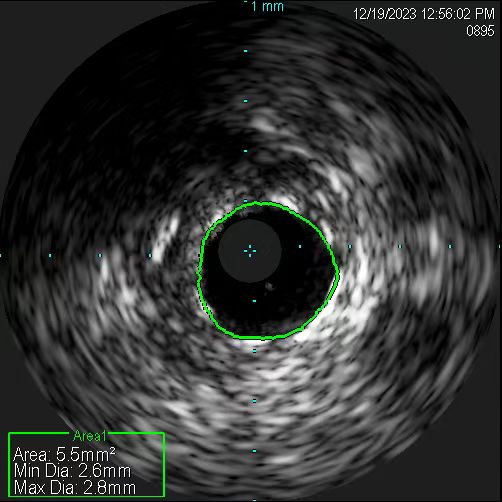

应用血管内超声精准测量。

在无造影剂显影情况下,冠脉导丝能否送达病变血管远端,是手术的关键一步。操作稍有不慎,导丝就可能误入分支,也可能穿出血管,引发致命后果。患者及家属的充分信任,是手术得以进行的先决条件。12月19日11时许,在具备手术条件时,张慧晶带领手术小组成员开始了挑战。术前各项准备完成后,韩世飞在李占虎协助下将指引导管顺利放置于右冠开口,他依据丰富的手术经验,将导丝成功送入到右冠远端,血管内超声(IVUS)探头顺利到位后便开始进行精准的检查。结果提示:患者右冠原支架贴壁良好、膨胀充分,进一步证实了此次犯病不是源于右冠。再行前降支IVUS检查,依靠上次冠脉造影图像作为参照,指引导管、主支导丝顺利到位,反复多次进行IVUS检查。张宏博根据IVUS图像及时进行精准的测量,前降支近段最小管腔面积2.7mm2,中段斑块负荷重,均达到处理标准;远段血管直径约2.5mm,近段血管直径约3mm。张慧晶带领大家根据IVUS检查结果,制定了详尽的支架植入方案:应用血管内超声的换能器精准测量,辅以分支导丝做为路标,一举将支架成功释放到理想位置。最终经IVUS检查提示:支架膨胀充分、贴壁良好,无残余狭窄及边缘夹层。历时近2小时,手术过程顺利,全程未使用一滴造影剂,患者未出现任何不适及并发症。术后复查心脏超声较前无变化,无心包积液,确定了无穿孔发生。